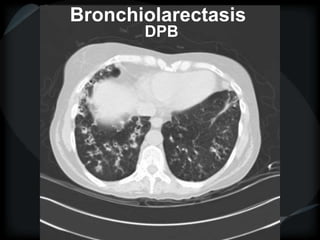

Bronchiectasis

Vessel at wall of cyst – signet ring

Cyst stacked in tubular orientation

Cyst stacked in branching pattern

Dilated, irregular, thickened airways

Mucus-filled airways

Diameter of peripheral airway to accompanying

artery = >1

● HGG ● CD

● ABPA ● tracheobronchomegaly

● CF ● α-1 antitrypsin deficiency

● DPB

Bronchiolarectasis

DPB